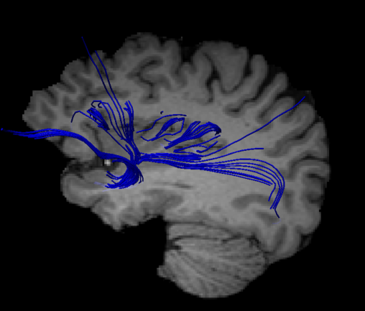

Resonancia magnética de la paciente con síndrome del acento extranjero. La flecha señala la disminución de fibras del fascículo fronto-occipital inferior a nivel de la ínsula medial, que coincide con la localización de la lesión estructural. / M. Berthier

Otra de las cuestiones sobre la que ha intentado arrojar luz este trabajo es la de conocer cuáles son las lesiones estructurales y funcionales del SAE. En concreto, la resonancia magnética descubrió pequeñas lesiones que afectaban especialmente al opérculo frontal y la ínsula interior, zonas del cerebro íntimamente relacionadas con la planificación de los mecanismos que permiten la iniciación del lenguaje y la articulación del palabras.

Berthier afirma que “las pruebas revelaron, entre otros indicios, una ruptura de los componentes clave de la red ligada a la planificación y ejecución de la producción del lenguaje, y a la propia comunicación emocional”. Junto a ello diversos indicios apuntaban a una ruptura de las vías colinérgicas —lateral y media— del cerebro como causa de la hipoactividad en esa región cerebral.